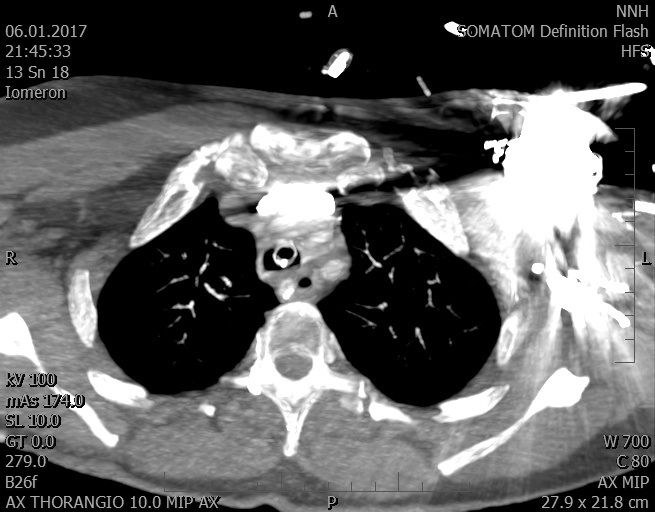

Video 1 - Akutní koronarografie prokázala normální nález na věnčitých tepnách s výjimkou suspekce na lehký spasmus na pravé koronární tepně.Echokardiograficky byla zjištěna těžká dysfunkce dilatované levé komory s nezvětšenou pravou komorou (video 2).

Video 2 - Echokardiograficky byla zjištěna těžká dysfunkce dilatační levé komory s nezvětšenou pravou komorou.Pro nejasnou příčinu zástavy jsme provedli i vyšetření výpočetní tomografií (CT), které vyloučilo plicní embolizaci (série 1 - soubory na konci článku). V den přijetí při přetrvávající oběhové nestabilitě byla nemocná opakovaně defibrilována pro fibrilaci komor se stabilizací rytmu po podání amiodaronu a mesocainu. Dle hemodynamických měření se jednalo o těžký kombinovaný šok. Vstupní laboratorní vyšetření bylo bez větších pozoruhodností. Posléze jsme doplnili anamnézu od příbuzných a zjistili, že pacientka užila do dvou hodin před srdeční zástavou první tabletu amoxicilinu na lehký respirační infekt. Při nevýtěžnosti vstupních vyšetření a nových anamnestických informacích jsme doplnili 14 hodin po kolapsu vyšetření koncentrace tryptázy v séru, která byla extrémně zvýšena (tabulka 2), což nás vedlo k podezření na anafylaxi.